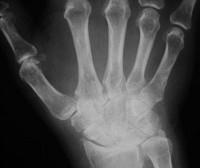

类风湿手X线(如图)的特点是 ( )A、软组织肿胀,关节变形B、关节游离体C、骨质硬化及增生D、骨质疏松E、关节间隙狭窄

问题 类风湿手X线(如图)的特点是 ( )

选项 A、软组织肿胀,关节变形 B、关节游离体 C、骨质硬化及增生 D、骨质疏松 E、关节间隙狭窄

答案 ADE